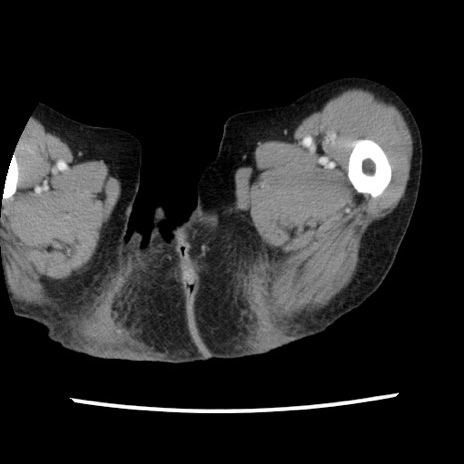

症例1(横断像)

【症例】80歳代女性

【主訴】腹痛

【現病歴】8時間前から腹痛あり来院。

【既往歴】糖尿病、脂質異常症、子宮体癌にて子宮全摘術

【身体所見】意識清明・会話良好だが腹痛で苦悶様、全腹部にわたって反跳痛と圧痛あり

【データ】WBC 13600、CRP 0.14、LDH 224、CK 90